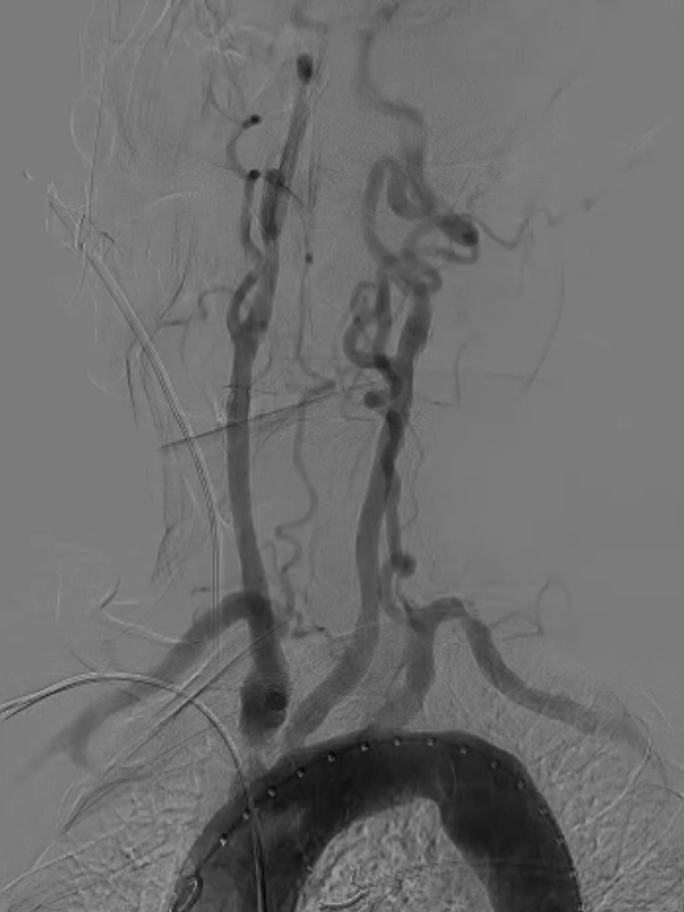

主动脉弓上造影显示无名动脉起始支架内重度狭窄,右椎动脉显影延迟,解除无名动脉支架内狭窄,恢复血流通畅,同时保障脑保护,降低并发症风险。

无名动脉起始支架内重度狭窄右椎动脉显影延迟

导丝与导管操作:超滑导丝配合多用途导管选入无名动脉,调整角度进入右锁骨下动脉;因主动脉弓扭曲严重,更换支撑导管通过病变段并造影证实

超选入无名动脉

无名动脉起始支架内

重度狭窄